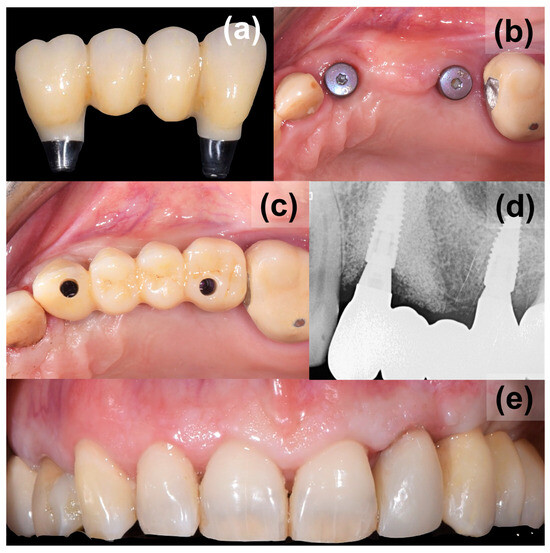

After another 3 months, following the verification of osseointegration, optical impressions were taken for the completion of the final prosthesis (Figure 4). After normal prosthetic phases, a screw retaining a three-unit bridge made of monolithic zirconia was applied (Figure 5). The occlusion and soft tissue compression were verified. After delivery, the occlusal function and soft tissue stability were monitored in the following months.

Figure 5. Application of final prosthesis, (a) a screw retained three-unit bridge made of monolithic zirconia, (b) final appearance of augmented site, (c) applied bridge, (d) control X-ray, (e) final aesthetics from the buccal view.